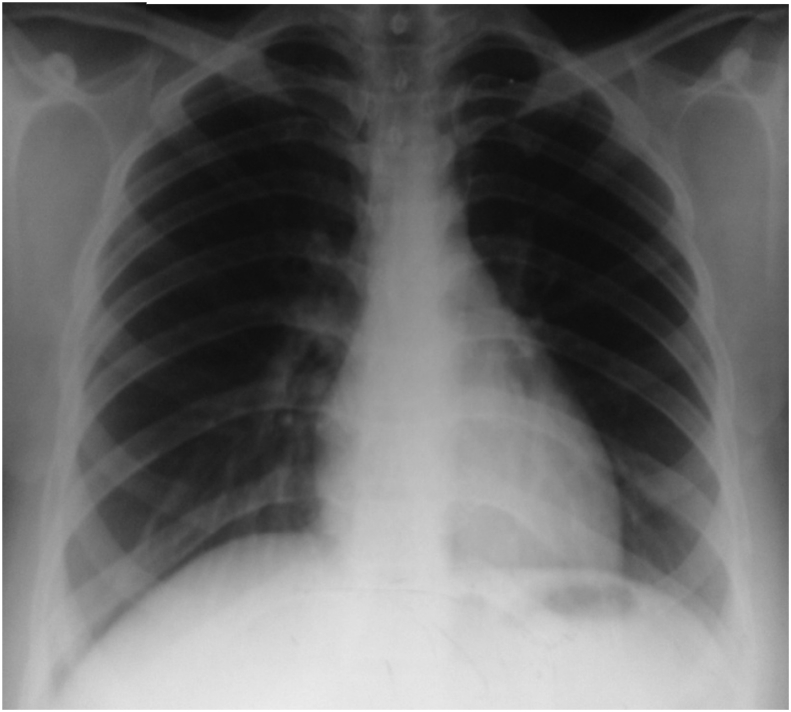

Chest radiograph (bedside anteroposterior view) showing bilateral military opacities and right paratracheal lymphadenopathy with left mid-zone consolidation.

Chest radiograph (posteroanterior view) showing complete resolution of opacities and right paratracheal lymphadenopathy at 6 months.